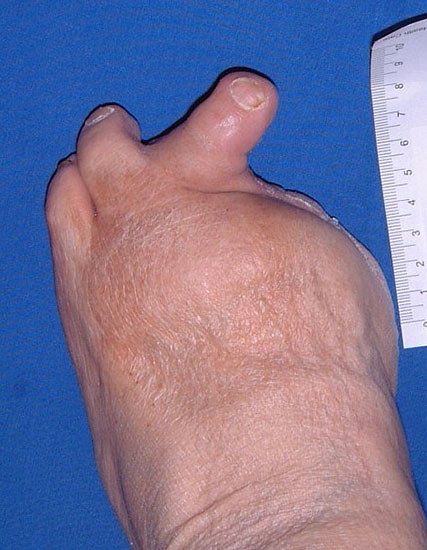

neuropathischer / septischer Fuß:

• Eitrig einschmelzende Infektion mit septischem Zustand = Notfallindikation (Abb. 2).

• Wenn eine Gangrän oder ein Abszess zu einem septischen Zustand, [Systemic Inflammatory Response Syndrom, (SIRS) Abfall von RR, PO2, Thrombos, Anstieg von PCO2, BZ] geführt und damit zu einer lebensgefährlichen Situation geführt haben, ist die unmittelbare Operation erforderlich (Tab. 1). Eine Drainageoperation oder eine Ausräumung der Infektion kann in der Frühphase der Sepsis erwogen werden, wenn der Eiterherd lokalisiert ist und keine ausgedehnten Destruktionen eingetreten sind. Wenn durch die Entlastungsoperation keine unmittelbare Besserung des Allgemeinzustands zu erwarten ist, besteht die Indikation zur Amputation.